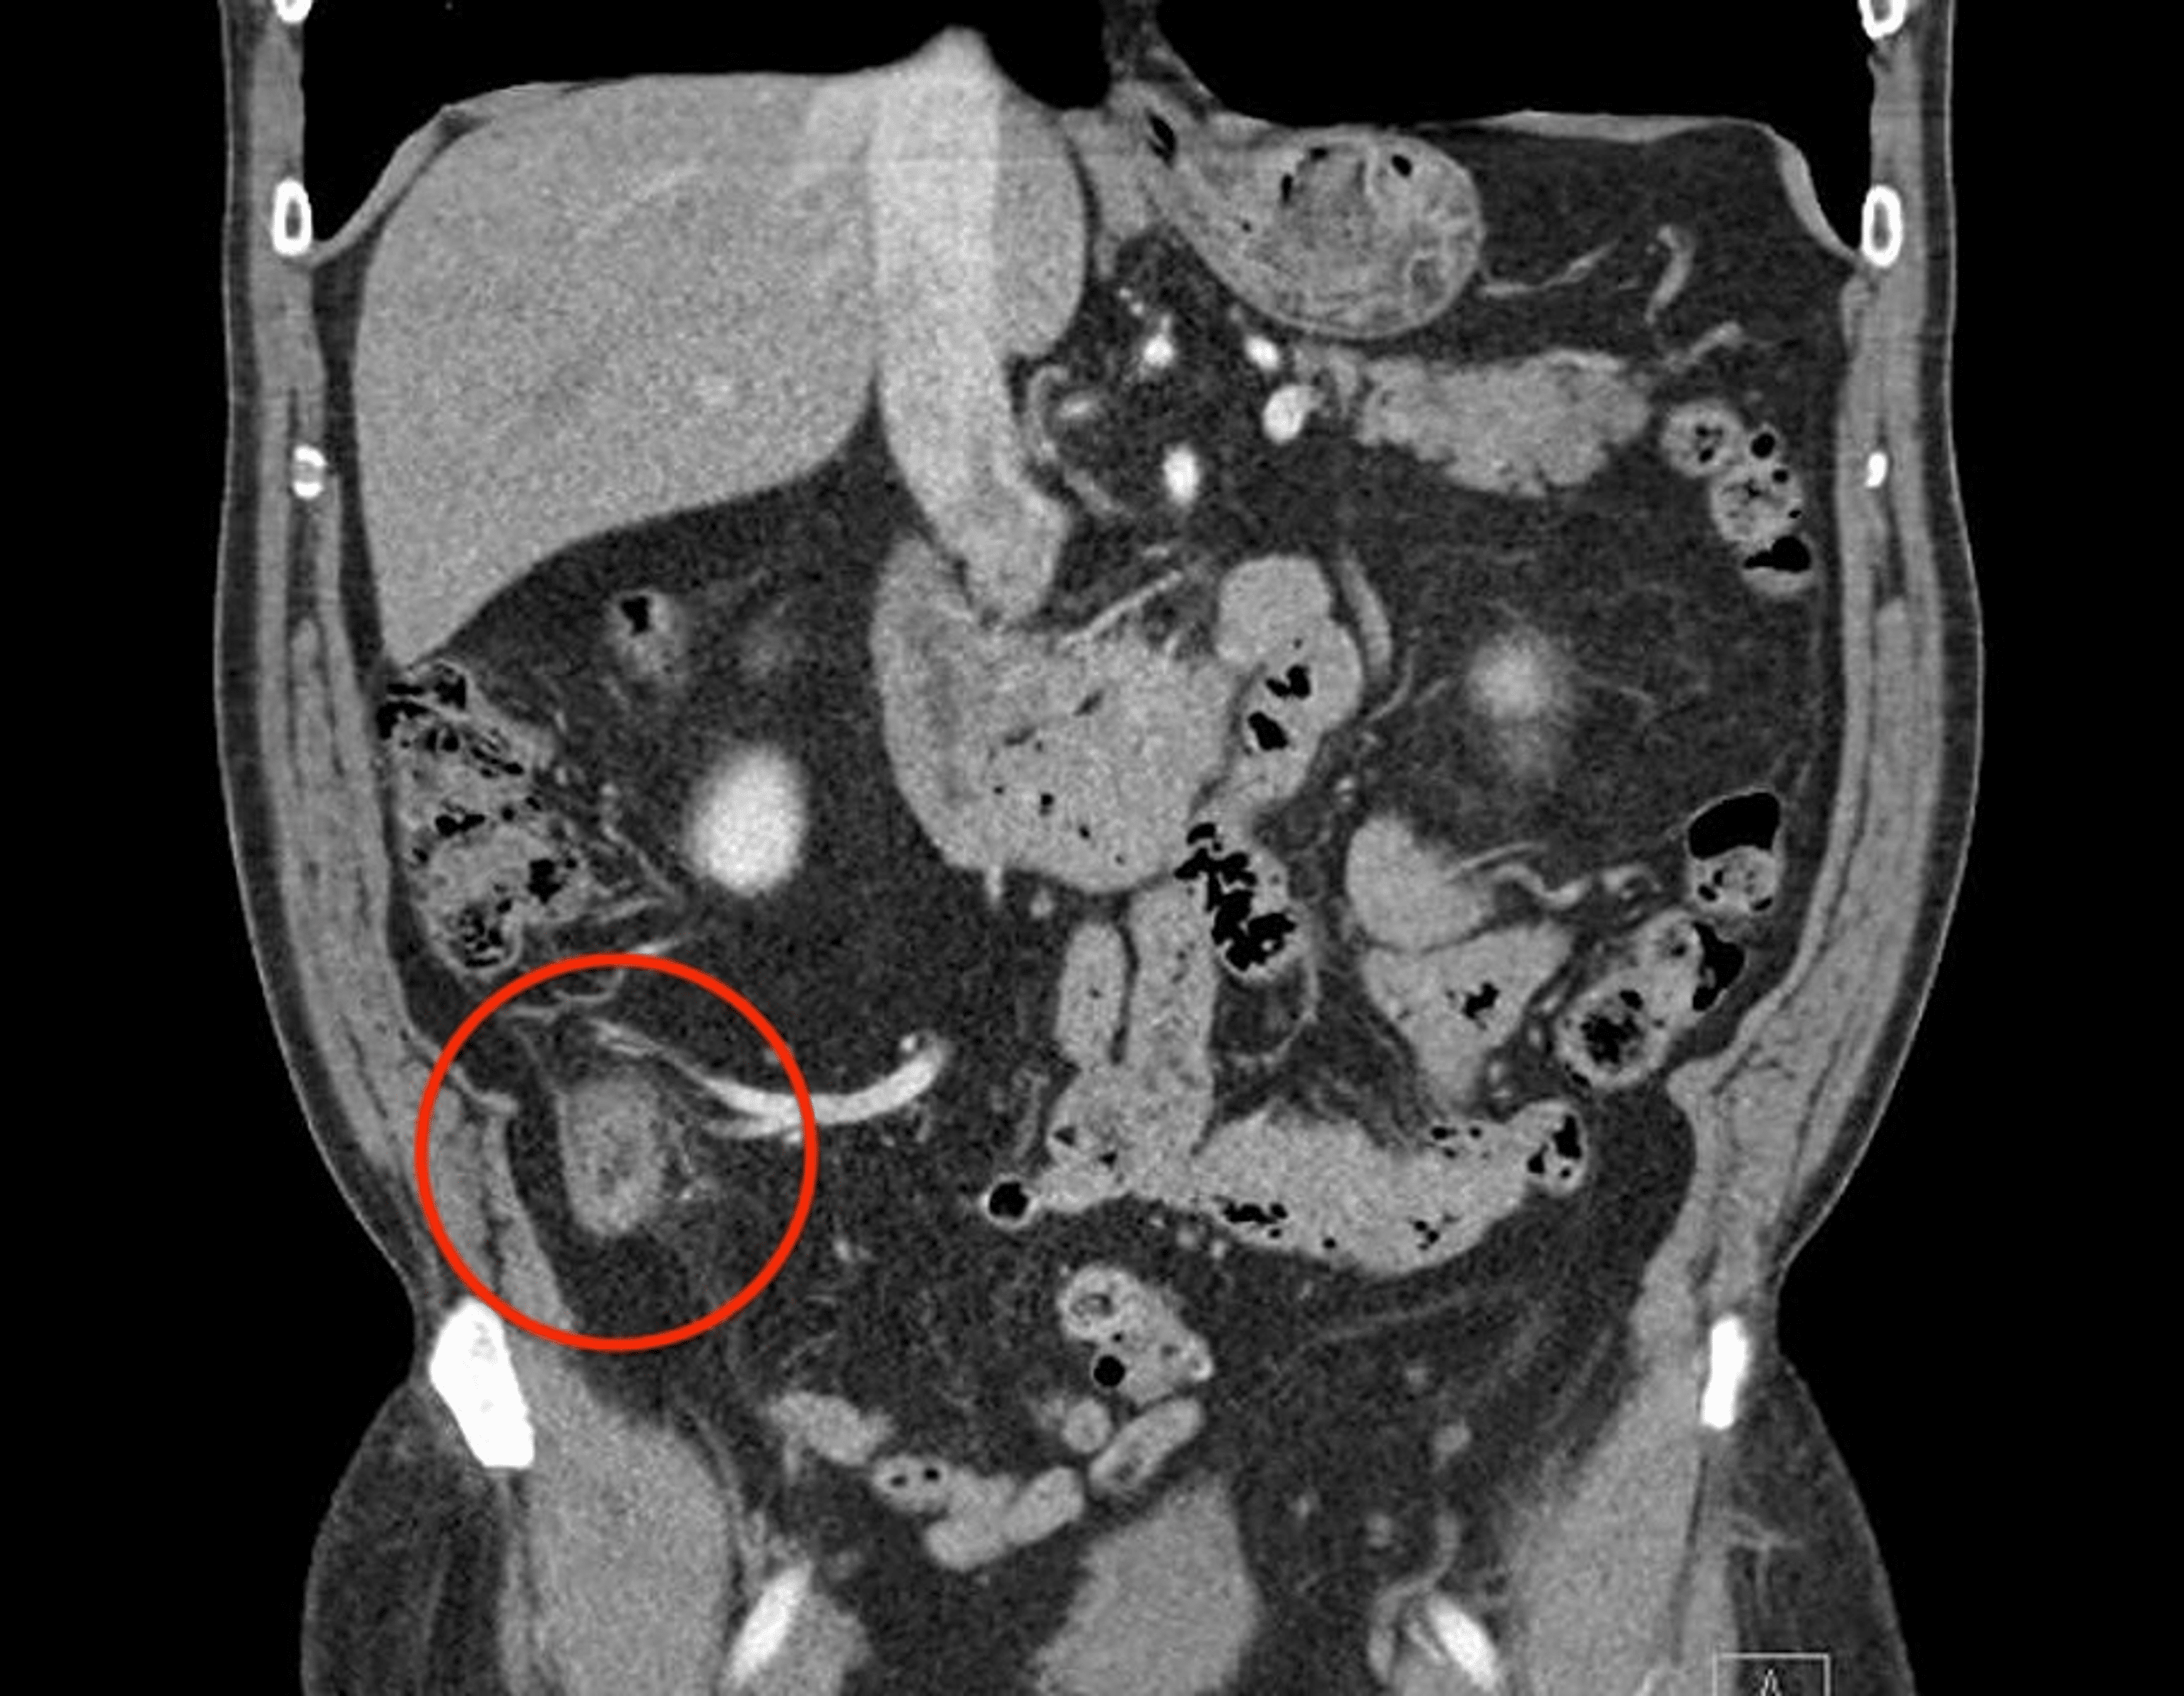

Dilated fluidfilled appendix with peri appendiceal inflammatory Turbid Fluid Appendicitis — larger quantities of fluid, especially if circumscribed and/or turbid, often accompanied by local or generalized paralytic ileus are. It is a very common condition in general. Diagnosing acute appendicitis accurately and efficiently can reduce morbidity and. — appendicitis is a common occurrence in both the adult and pediatric populations. — signs and symptoms. For diagnosing acute. Turbid Fluid Appendicitis.